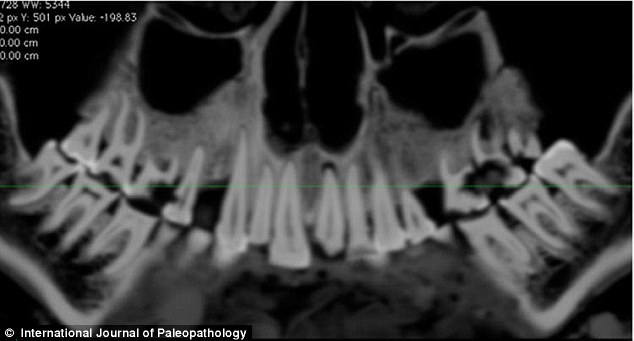

上圖是木乃伊口腔CT掃描圖,可以看到亞麻布團(tuán)被填充在右部。

《古病理學(xué)國際期刊》的文章稱,來自加拿大西安大略大學(xué)的安德魯·韋德利用一種新型高分辨率CT儀掃描木乃伊的牙齒和身體,并且根據(jù)掃描片重建了3D圖以進(jìn)行更為細(xì)致的研究。從CT掃描片可以看到,木乃伊的一顆牙齒齲洞里塞著一塊亞麻布團(tuán)。這塊亞麻布之前可能經(jīng)過無花果汁液或雪松油等藥物的浸泡,隨后被塞入下顎第一、二顆臼齒中間,也就是最大、也是最疼的齲洞里。這么做既能起到抵擋食物殘渣進(jìn)入齲洞的屏障作用,又能利用亞麻布上的藥物緩解疼痛。